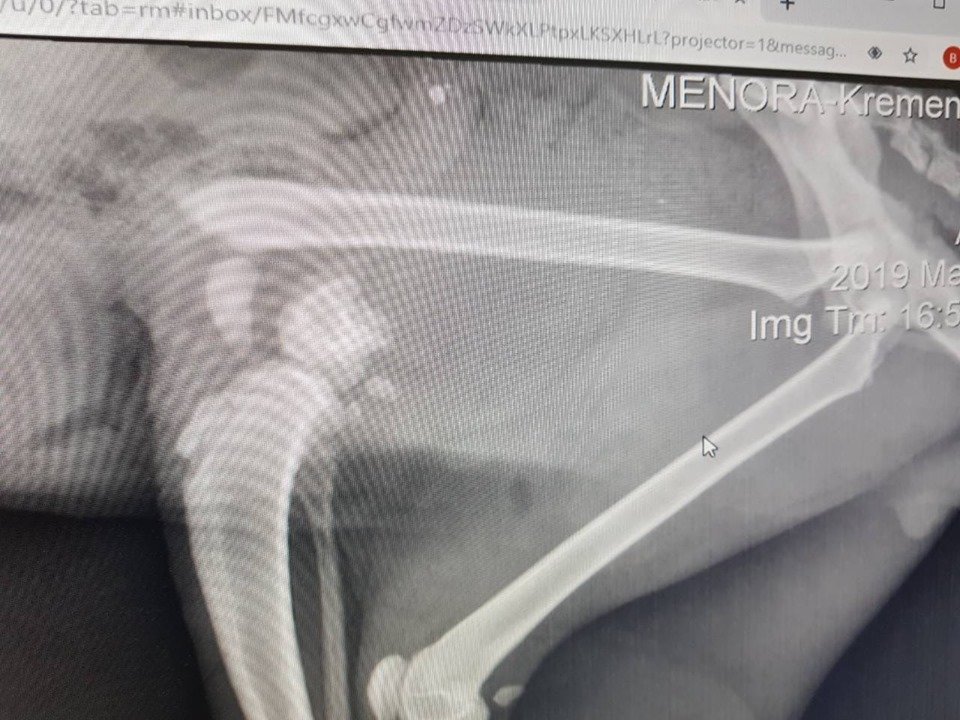

– Як це сталося, ми не знаємо, але у кота дуже серйозна травма задньої лапи. Після обстеження і рентгена з’ясувалося, що потрібна термінова операція. Сьогодні кота прооперували в клініці Зооветцентр. Спасибі, лікарю, ви зробили неможливе! Реабілітаційний період триватиме понад місяць, адже перелом був дуже складним і зламану кістку скріпили спицею. – зауважила Марина Кожушко.